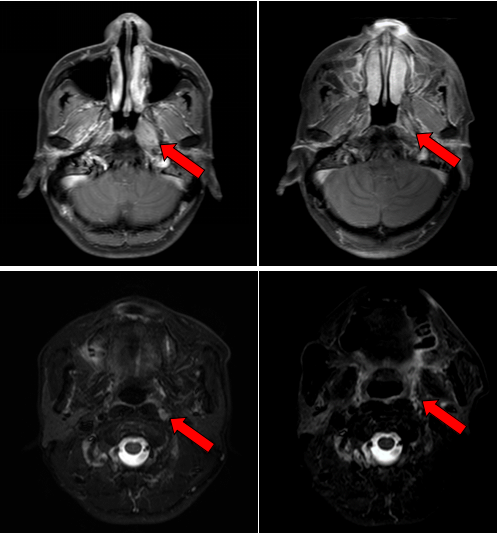

2016年7月,患者因左侧耳鸣一个多月到医院就诊,经过一系列检查,最终确诊为鼻咽非角化性癌,分期为T3N1M0 Ⅲ期,属于局部晚期鼻咽癌。我院鼻咽癌诊治中心邱素芳主任医师团队接诊后,为其量身制定了“诱导化疗+同步放化疗+辅助化疗”综合方案,在放疗环节凭借精细靶区勾画与剂量调控,实现“精准打击”。治疗结束后复查,肿瘤已基本退缩。

治疗前后鼻咽部病灶、咽后淋巴结病灶对比( 左:治疗前,右:治疗后)